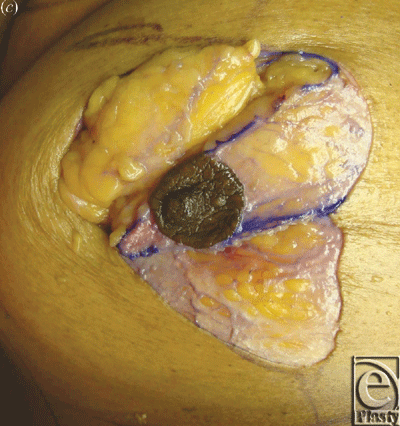

The breasts were approached either using a short vertical skin incision as described by Lejour and Abboud6 or via a periareolar skin incision. Surgical steps included skin incision, deepithelialization, and intraoperative marking of the planned glandular Z-plasty. The angles were chosen depending on breast size, shape, and degree of ptosis. The gland was then incised according to the form of the Z; flaps were undermined and transposed; and the inferior flap carried the nipple superiorly. For left-sided breasts, the Z was a mirror image of the right. For the short vertical skin incision group, the flaps were fully transposed. For the periareolar skin incision group, the flaps were partially transposed such that the superior flap was inset under the inferior Nipple bearing flap; this provided auto-augmentation. After glandular transposition of varying degrees and inset, the skin incision was then closed in the usual fashion. Photographs were taken to compare the breast appearance before and after the procedure (Figs 1 and 2), and the overall aesthetic appearance was graded on a scale from 1 (worst) to 5 (best).

The inferior limb transposition moved the nipple superiorly and medially closer to the sternal notch and sternum midline an average of 5.3 ± 2.2 cm and 2.4 ± 1.7 cm, respectively. The average Z-plasty degree was 34.5 ± 8.2°. The average central limb length 8.7 ± 2.1 and average pedicle width was 5.4 ± 0.8 cm. An average of 1.8 perforators greater than 1 mm in diameter were visualized and divided to freely mobilize the inferior limb of the Z (ie, superior-medial pedicle with nipple). Buttress support of the nipple was accomplished by the caudal transposition of the superior Z-plasty flap and its inset below the nipple. A Benelli block technique was used to create a purse-string suture in the periareolar group before final skin closure. Finally, the average overall aesthetic result was 3.3 ± 0.9; the average vertical scar aesthetic result was 3.0 ± 0.8; and the average periareolar aesthetic result was 3.6 ± 1.0 (P = .2). Table 2 summarizes the aforementioned findings.

Theoretically, a Z-plasty will reorient and lengthen the central limb of the breast, which would be counter-productive to the goal of a lift. We did not record any lengthening effect; in fact, the breast was determined to be smaller in all dimensions, including width, length, and height. By planning the inferior flap of the Z-plasty to include the nipple, a superomedial pedicle is naturally created, and upon transposition is superiorly rotated into an elevated position. In addition, the superior Z-plasty flap is inset in such a way that it acts as internal support or buttress.